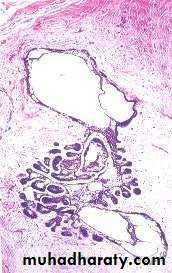

• Adenomatoid tumor

• Histopathology:• Sheets or islands of epithelial cells arrange around microcyst ( Ducts or ductules ) .

• Surrounded by thin vascularized stroma .

• The ductules bordered by ameloblast like cells .

• The lumen filled by homogenous

• eosinophilic material .

• Small foci of calcification .